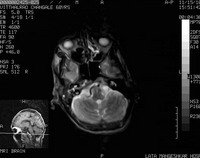

AbstractRamsay Hunt syndrome (also termed Hunt's Syndrome and herpes zoster oticus) is a herpes zoster virus infection of the geniculate ganglion of the facial nerve. It is caused by reactivation of herpes zoster virus that has previously caused chickenpox in the patient. Ramsay Hunt syndrome results in paralysis of the facial muscles on the same side of the face as the infection so, the virus infects the facial nerve that normally innervates the muscles of the face. Ramsay Hunt syndrome is typically associated with inflamed vesicles in or around the ear and sometimes on the roof of the mouth or tongue. Here we are presenting a case of 70 year old male had Ramsay Hunt syndrome with multiple cranial nerves' involvement (CN IX & X). Treatment with prednisolone and valacyclovir was given within the first three days of facial paralysis to the patient to achieve complete recovery. IntroductionRamsay Hunt syndrome is defined as varicella zoster virus(VZV) infection of the head and neck that involves the facial nerve, often the seventh cranial nerve (CN VII). Other cranial nerves (CN) might be also involved, including CN VIII, IX, V, and VI (in order of frequency). This infection gives rise to vesiculation and ulceration of the external ear and ipsilateral anterior two thirds of the tongue and soft palate, as well as ipsilateral facial neuropathy (in CN VII), radiculoneuropathy, or geniculate ganglionopathy. After chickenpox, VZV remain latent in neurons of cranial nerve and dorsal root ganglia. Subsequent reactivation of latent VZV can result in localized vesicular rash, known as herpes zoster. VZV infection or reactivation involving the geniculate ganglion of CN VII within the temporal bone is the main pathophysiological mechanism of Ramsay Hunt syndrome. Here we are presenting a rare case of Ramsay hunt syndrome with multiple cranial nerve involvement. Case reportA 70 year old male, right handed, farmer by occupation presented with fever and erythematous rash over external ear since 3 to 4 days, difficulty in swallowing, deviation of angle of mouth to left side since 2 days , unable to close right eye , hiccoughs and headache since 1 day. There was no history of any ear discharge, convulsion, unconsciousness or weakness in any limb. Patient denies any history of hearing loss. There was no history of diabetes mellitus, hypertension, pulmonary tuberculosis, patient also denies any history of promiscuous behavior. On general examination patient was conscious oriented with time, place and person, Afebrile, P - 84/min regular RR-20 / min, BP- 100/60 mm Hg, Pallor present. On cutaneous examination multiple grouped vesicular eruptions on erythematous base presented on external ear and posterior aspect of right ear (Figure1&2). On systemic examination within normal limits. CNS examination within in normal limits except VII, VIII, IX, X cranial nerves were involved. Patient had right side palpebral fissure widen than left, incomplete closure of right eye, nasolabial fold flattening on right side, angle of mouth deviated to left side, epiphora from right eye, taste sensation of anterior 2/3rd of tongue was absent suggestive of VII cranial nerve(facial nerve) involvement. Rinne's test positive in both ears, Webers test showed reduced hearing on right ear suggestive of sensorineural hearing loss of right side of VIII cranial nerve(Vestibulocochlear nerve) involvement. Soft palate movements on right side were absent, gag reflex absent on right side, uvula was deviated to left side suggestive of IX & X cranial nerve (Glossopharyngeal & Vagus nerve) involvement. Other cranial nerves were normal. Motor function & delayed tendon reflexes were normal. Sensory function was normal. Cerebellar functions were normal. Fundus examination was within normal limit. On clinical examination was consistent with acute onset lower motor neuron type right sided VII,VIII, IX, X cranial nerve palsy due to reactivation of herpes zoster. Then we investigated the patient as CBC- Hb-10 mg/dl, KFT- Urea -30mg%, Sr.creatinine-0.8%, LFT- normal, HIV 1 &2 - negative, blood sugar (random)-104 mg/dl. Serology results for herpes simplex virus 1 and 2 were positive for IgG antibodies and negative for IgM antibodies. Varicella-zoster virus (VZV) IgG antibodies were positive, but IgM antibodies was positive. MRI brain revealed age related mild cerebral atrophy with neurodegenerative changes. Soft tissue intensity was seen in right mastoid air cells and in the inner cavity which on post contrast study showed minimal enhancement with edematous VIIth and VIIIth nerve complex suggestive of inflammatory focus in clinically diagnosed case of Ramsay Hunt Syndrome (Figure 5). The patient was treated with tablet valacyclovir 1gm 3 times per day for 7 days along with tab prednisolone 40 mg OD in tapering dose for 1month, Ryle's tube feeding was done for 10 days, Physiotherapy of facial nerve was done for 1 month, eye bandage was put for 10 days. At the end of 1 month remarkable improvement was observed (Figure 1,2,3,4 & 6,7 shows pre treatment & post treatment photograph). He is being followed up till today.